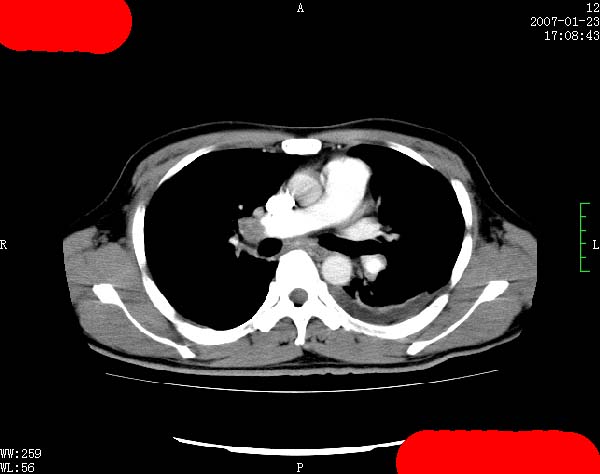

以下是引用jiangjing在2007-1-24 23:35:00的发言:[br]支持 增强扫描见右肺动脉干、左下肺动脉见充盈缺损。印象为:1、右肺动脉干、左下肺动脉栓塞。 2、左侧胸腔积液合并左肺下叶被动性肺不张。

以下是引用rjg199343在2007-1-24 23:22:00的发言:[br]增强扫描见右肺动脉干、左下肺动脉见充盈缺损。印象为:1、右肺动脉干、左下肺动脉栓塞。 2、左侧胸腔积液合并左肺下叶被动性肺不张。